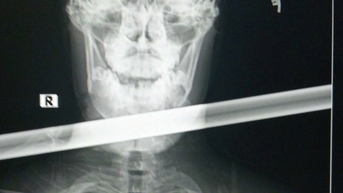

턱과 목에 1.2m 길이의 철봉이 박힌 청년 구출

Báo Tuổi Trẻ

09/01/2025